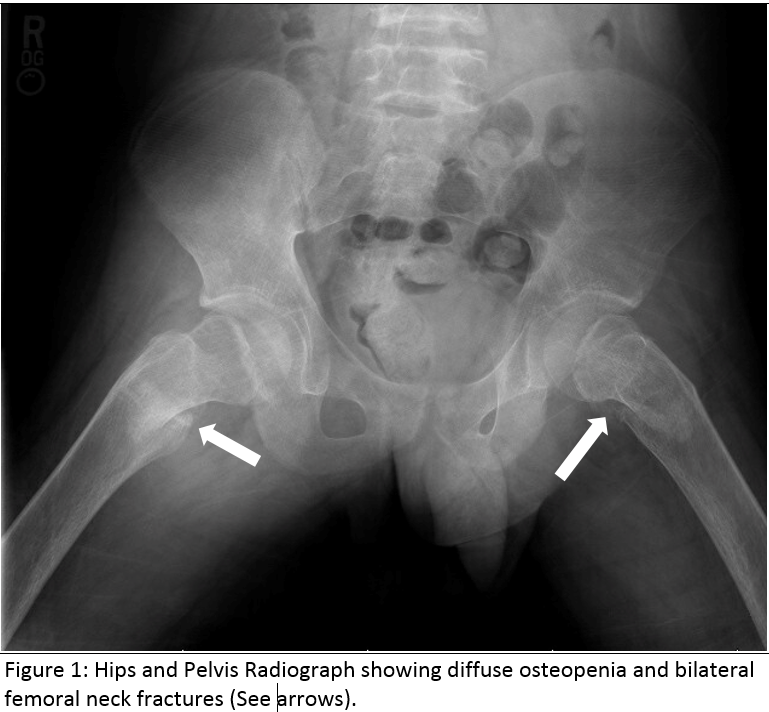

Case Presentation: A 14-year-old male presented to an emergency department with 6 days of left thigh pain and inability to bear weight following a fall from bed. Associated symptoms included nausea, diaphoresis and weakness. Review of systems revealed pallor, easy bruising and yellow eyes. history was negative except for developmental delay, described as auditory processing issues. He had no prior hospitalizations or significant family history. Physical examination showed normal vital signs and growth parameters, poor dentition, mild scleral icterus, pallor and a I/VI systolic ejection murmur. Liver was palpable 2 cm below the costal margin. The left lower extremity (LE) was externally rotated and flexed at the hip. Both LEs had limited range of motion at the hip due to pain. Tenderness to palpation of the left thigh was noted. Exam was otherwise normal. Initial workup revealed normocytic anemia and mild hyperbilirubinemia (Table 1). Left femur, pelvis and bilateral hip x-ray showed bilateral femoral neck fractures and diffuse osteopenia, suggestive of metabolic or infiltrative disorder (Figure 1). MRI Pelvis showed bilateral femoral fractures, abnormal enhancement of hip and thigh muscles, and hip joint synovium. Leading differential at this time included malignancy or infectious process. Further labs demonstrated elevated inflammatory markers, but normal lactate dehydrogenase (LDH), uric acid, peripheral smear, haptoglobin and red blood cell studies. Parathyroid hormone was elevated and vitamin D was low.